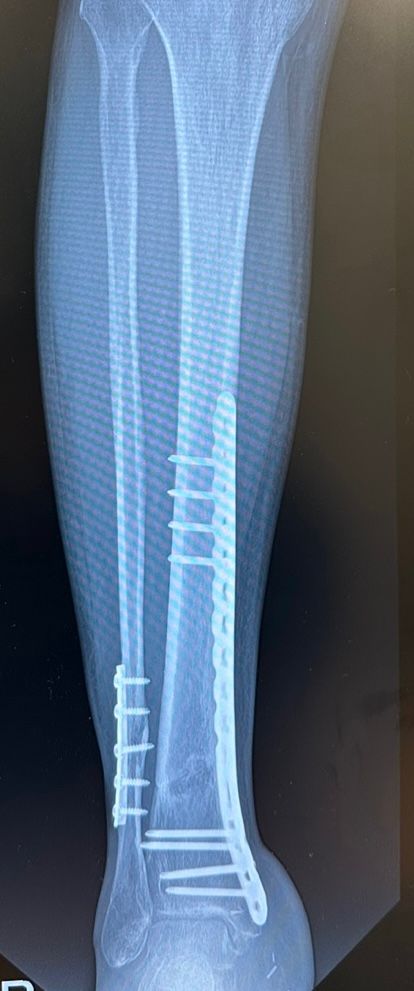

골절 후 엑스레이상 지금 상태가 어떤가요?

선생님 말로는 심하게 골절되어 시간은 좀 걸리지만 잘 붙고 있다고하는데 맞나요?

아래 엑스레이 상 뼈조각 같이 보이는건 뭔가요??

• 1번 째 사진

골유합은 잘 진행이 되고 있으신 것 같습니다.

뼈조각 처럼 보이는 것은 실제로 골절편이 전위되었을 가능성 및 골유합 과정에서 뼈찐 등이 퍼져나갔을 가능성도 있으나 치료과정에 큰 영향은 없으실 것 같습니다.